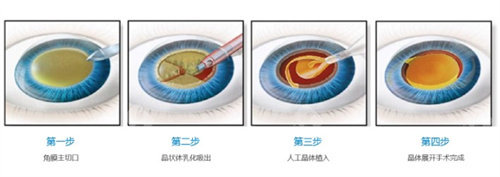

政策执行遵循“便民、有效”原则,流程拆解为四个关键步骤,每个环节都有明确的时间要求与操作规范。

头一步为申领表格,申请者需携带身份证与户口本前往户籍所在地社区,领取《光明行申请表》,表格填写需确保信息真实正确,避免因信息误差影响审批进度。

第二步是免费筛查,领表后需前往指定机构完成眼部检查,筛查内容包括视力检测、晶体混浊程度评估等,用于确认是否符合手术条件。筛查工作覆盖呼市9个旗县区,申请者可选择就近机构,减少奔波。

第三步为审批报备,填写完整的申请表需经社区盖章确认,随后提交至相关部门审核,审核周期为3个工作日,审批结果会通过电话或书面形式通知申请者。

第四步为手术安排,审核通过者需在接到通知后7天内入院,超期未到将视为自动放弃,需重新排队申请。手术时间由相关部门统筹安排,遵循“就近、便利”原则,结合患者病情与机构资源合理调度。

医疗服务不仅包括手术本身,还涵盖术前评估、术中操作与术后随访三个环节。术前评估会详细告知患者手术方案、潜在风险与术后注意事项,确保患者知情权;术中由专科医师团队操作,遵循标准化的诊疗规范;术后随访则是确保改善成效的关键,免费随访周期通常为术后1个月内,期间医生会监测视力修养情况,及时调整护理方案。